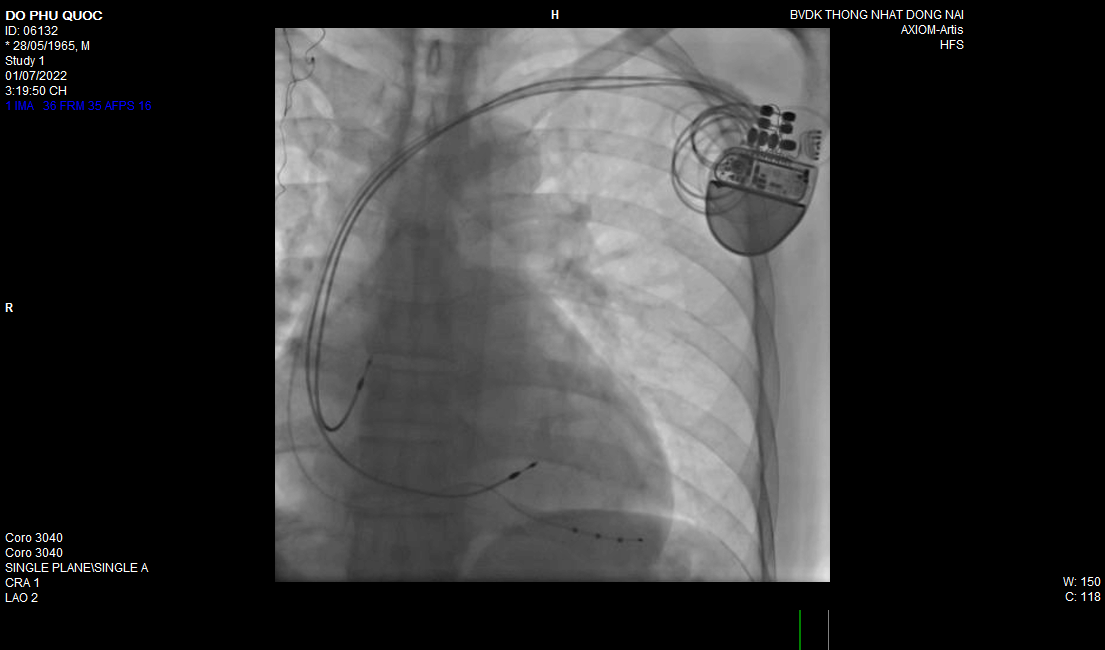

5.5 Tạo nhịp tim tạm thời và vĩnh viễn:

Tạo nhịp cấp cứu tạm thời, cấy máy tạo nhịp vĩnh viễn 1-2 buồng giúp phòng ngừa các biến chứng của nhịp chậm do suy nút xoang, bloc nhĩ thất nặng. Cấy máy phá rung tự động (ICD) ngăn ngừa đột tử do loạn nhịp thất ác tính. Cấy máy tái đồng bộ tim (CRT-P, CRT-D) hỗ trợ điều trị suy tim kháng trị…

Một trường hợp cấy máy CRT-P Boston-Scientific hỗ trợ điều trị suy tim nặng, kháng trị